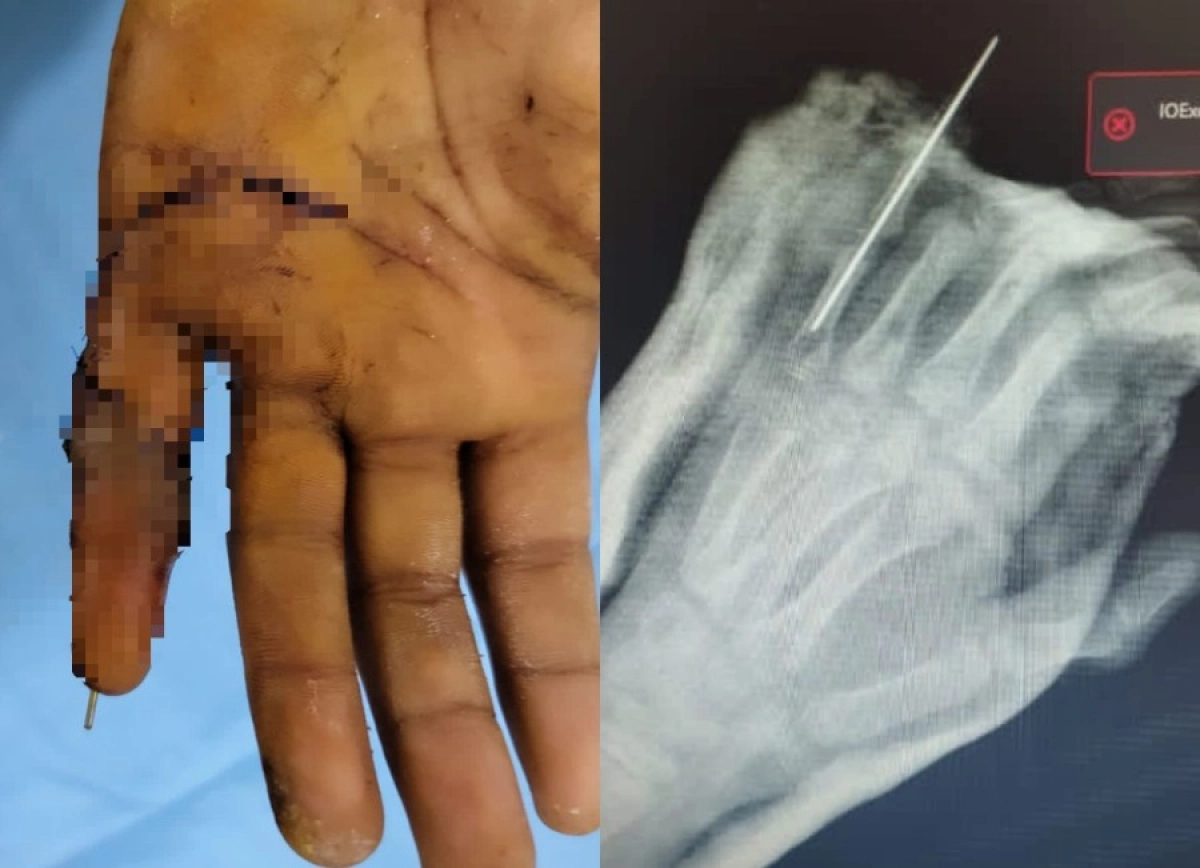

В детской городской клинической больнице №2 Алматы впервые произвели сложнейшую операцию по реплантации пальца кисти ребенку — 9-летнему мальчику пришили палец руки, отчлененный в результате уличной травмы. Экстренную операцию выполнили заведующий отделением травматологии Ерлан Садырбалин совместно с микрохирургами Сергеем Косаревым и Александром Смолянкиным. Шансы спасти палец были крайне малы, передает ИА «NewTimes.kz».

Операция длилась непрерывно около пяти часов. Это очень кропотливая работа. Врачи делали все возможное, чтобы сохранить палец. Они под операционным микроскопом сшивали ткани и сосуды, соединяли поврежденные пальцевые артерии, нервные волокна очень малого диаметра, были восстановлены кость, сухожилия, вены и кровообращение в присоединенном пальце.

«Для проведения такой операции необходима современная микрохирургическая техника: требуется микроскоп, микрохирургический инструментарий и очень тонкий шовный материал, который сложно увидеть невооруженным глазом, все это имеется у нас во 2-й детской больнице. Нам пришлось шить сосуды диаметром 1,2 мм. Без должной подготовки, оборудования, инструментов и расходных материалов проведение таких операций невозможно», — рассказал заведующий отделением травматологии ДГКБ №2 Ерлан Садырбалин.